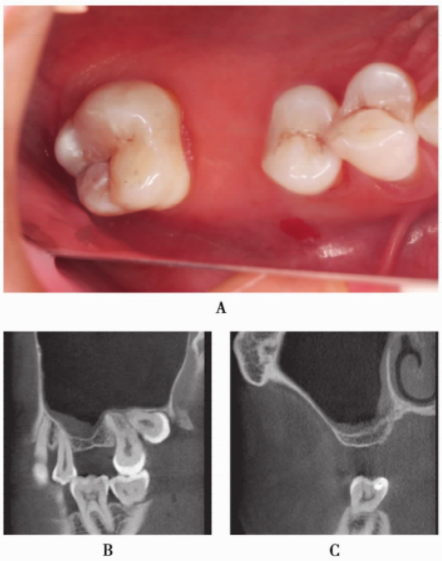

患者,女性,58岁,B7缺失,B6Ⅲ°松动。数码全景片示B6根折,根尖周阴影明显,骨质缺损明显(图17)。

图17 数码全景片(局部)显示B6牙槽骨吸收明显

因为B6根尖和牙周炎症较重,拔牙后没有即刻行拔牙位点保护术。拔牙2个月后,外提升术前CBCT示骨质缺损明显,剩余骨量不足以进行种植体植入(图18)。

图18 同一患者拔牙后2个月CBCT,骨量明显不足A.矢状位;B冠状位;C水平位